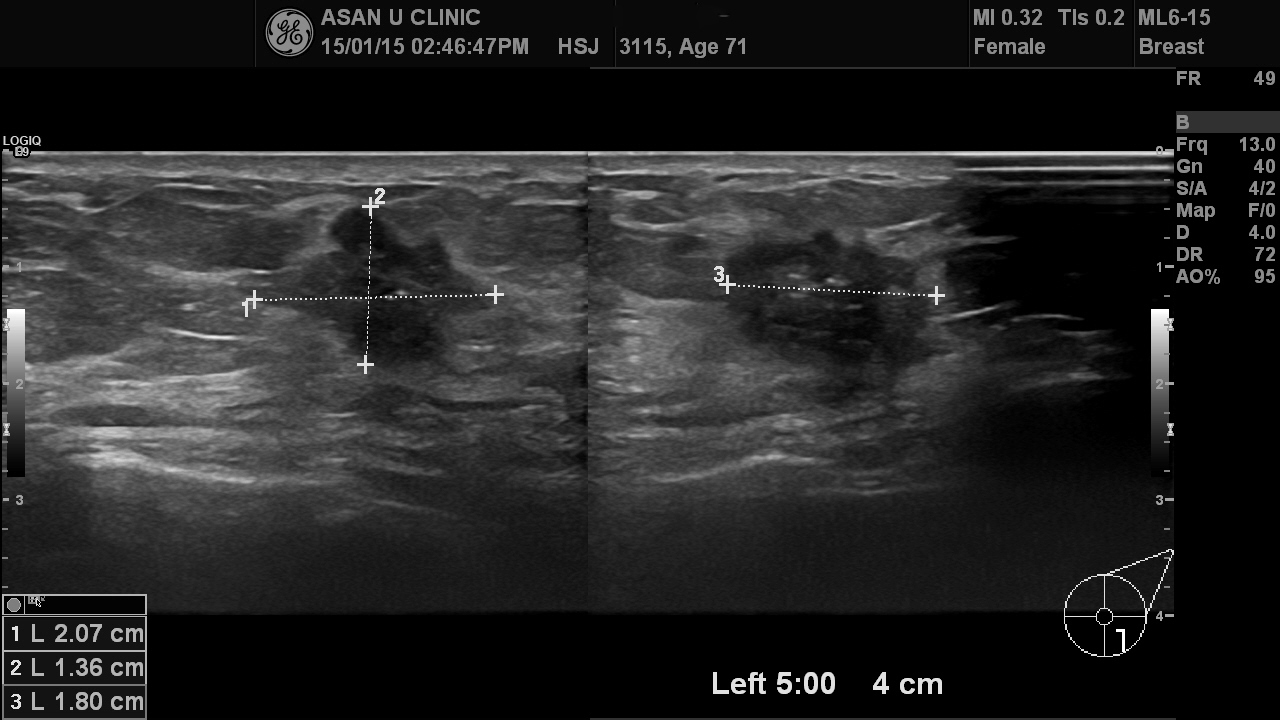

건강검진 이상으로 내원한 71세 여성분입니다.

초음파상 2cm가 넘는 혹이였으나

중심핵생검으로 좌측 유방에 침윤성 유관암이 진단되었습니다.

다행히 초음파로 보기에는 겨드랑이까지 림프절 전이는 없어 보입니다.